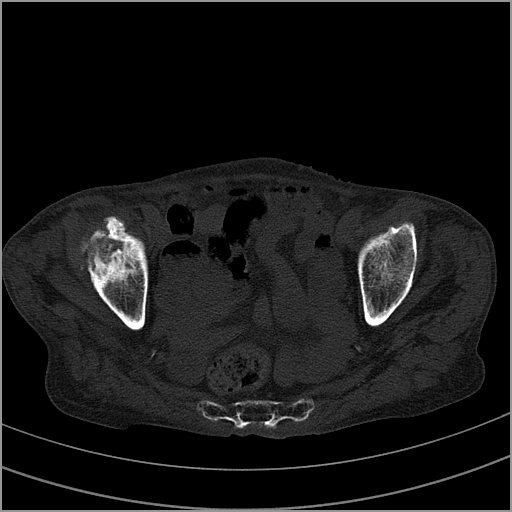

以下是引用老爱克斯新网客在2009-2-3 19:42:00的发言:[br]右侧髋臼及右侧股骨头可见明显骨质破坏,以溶骨性破坏为主,无明显硬化,髋关节间隙变窄,周围软组织明显肿胀,密度不均,脂肪间隙消失。[br] 诊断:右侧髋关节感染性病变,右侧髋关节结核的可能大。[br] 鉴别诊断:1.股骨头缺血坏死,单纯股骨头缺血坏死病例不会累积髋臼骨破坏。2。退行性关节炎,以骨质增生为主,伴有关节面硬化,骨质破坏呈多发小囊状破坏为主,其周围可见硬化环。3.股骨头缺血坏死晚期(第四期)骨质破坏可伴髋关节退行性变,可有骨质增生,但此时骨破坏以股骨头破坏为主,不应该伴有髋臼骨质破坏,因为股骨头的骨破坏是因血运中断,而没有髋臼的血运中断,又没有细菌的感染,怎么能造成髋臼的骨破坏呢。